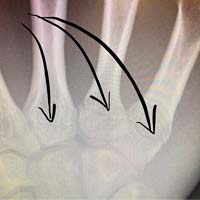

A pesar de un intenso dolor que auguraba lo peor para Annika Langvad, las pruebas realizadas en el hospital confirmaron que no hubo rotura alguna de huesos o cartílagos en su mano. Según explica la propia corredora a través de las redes sociales: "No es exactamente como me imaginé la carrera del domingo. Fui derribada en una caída masiva en el comienzo de la Copa del Mundo de Val di Sole. La buena noticia es que nada está roto pero... ¡Oh chicos! ¡Cómo me duele la mano! Por suerte, solo tengo que esperar y ver la evolución los próximos días. Eso es correr. Rodamos muy cerca y apretados y los accidentes pueden pasar, son parte del juego. ¡Me alegro de no haber terminado mi temporada aquí!".